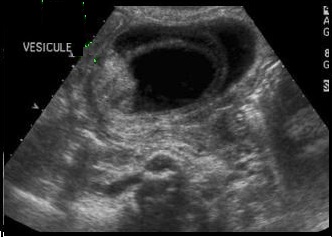

Image echographique : Image

echographique a susgestion de syndrome Mirizzi est image d'une

calcule en coince a infundibulum de la vesicule biliaire ou

intraluminal du canal hepatique commun . Une dilatation de

voie biliaire principale et et des voies biliaires

intrahepatiques en amont est souvant se presente .Et image d' une inflammation chronique de

vesicule biliaire etre en voyait

Image echographique

d'une calcul du collet vesiculaire compressee sur

le canal hepatique commune . Les voies biliaires en

amont sont dilatees . Vesicule biliaire est en

inflamee a paroi tres epais ( cholecystite chronique

) :: Syndrome de Mirizzi |